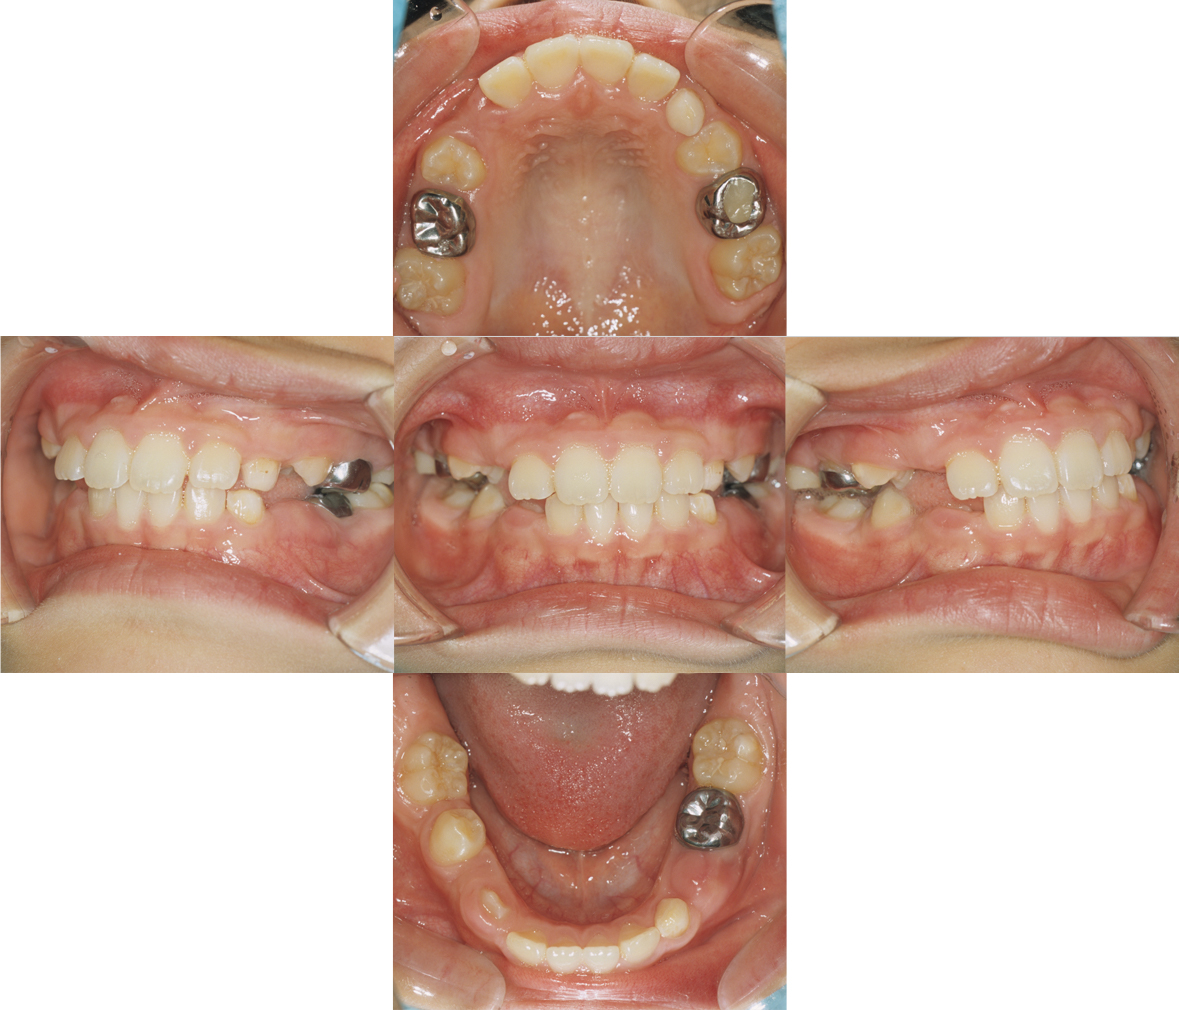

主訴

歯並び

主症状

叢生および上顎前突

初診時年齢

11歳 女性

治療期間

Ⅰ期治療:1年0か月、Ⅱ期治療:1年4か月

治療費

装置料 Ⅰ期治療30万円、Ⅱ期治療 25万円 処置料 4,000円×12 回、 5,000円×16回(税抜)

治療内容

非抜歯治療で行う目標を立て、Ⅰ期治療でヘッドギアにて上顎第一大臼歯を後方に移動させた。Ⅱ期治療を非抜歯にてマルチブラケット装置を使用して治療を行った症例。

リスク

ヘッドギアをきちんと使用しないと歯が動かず、Ⅱ期治療において小臼歯抜歯による矯正治療が必要になる。歯ブラシが不十分であると治療中に虫歯や歯肉炎をおこし、治療期間も余計にかかることがある。装置撤去後に保定装置をきちんと使用しないと後戻りを起こす。

■初診

■第1期治療終了時

■第2期治療終了時